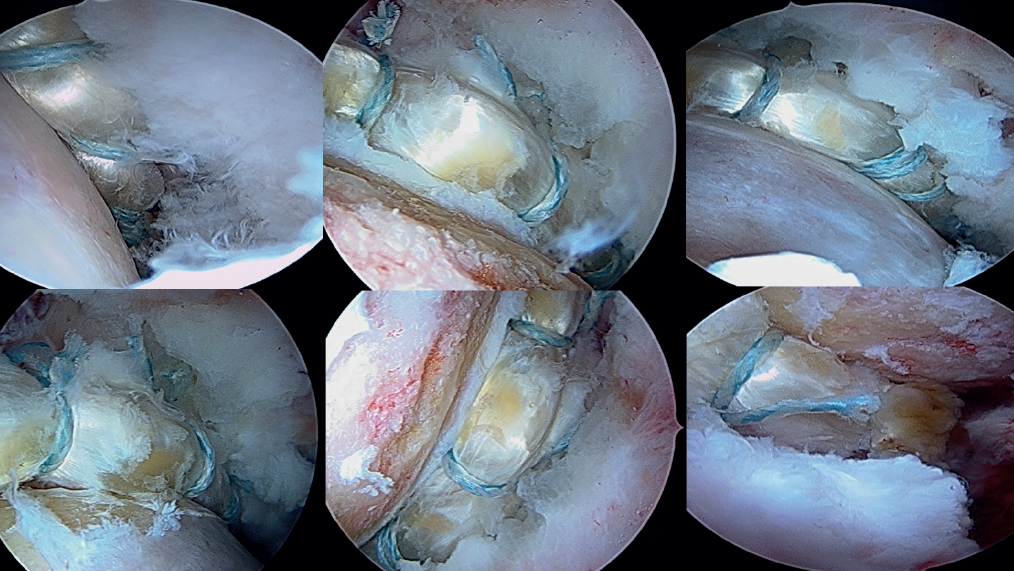

From the modified anterior portal, pre-drilling is performed at the 4 o'clock position (Figure 7) to implant an anchoring, with two possible variants: PressFT® 2.8 mm (Conmed), or an all-filament anchoring followed by threading of the extremity. Then, and also through the modified anterior portal or from the medial oblique portal, the first FiberTAK® Knotless 1.8 mm tensioning (Arthrex) anchoring is positioned 1 cm from the most anterior pre-drilling or anchoring, and its filaments are retrieved through the medial oblique portal. The successive FiberTAK® Knotless sutures are introduced through the medial oblique portal until reaching the posterior zone at the 8 o'clock position (Figures 8 and 9). During perforation and pre-drilling of the anchoring, the arthroscope is to be placed in a position allowing assessment of the joint cartilage, in order to make sure that the drill is not located between the subchondral bone and the surface of the joint cartilage. In order to prevent the anchorings from penetrating into the acetabular cartilage, the angle of the margin must be determined to ensure adequate placement. Lastly, the most posterior anchoring is introduced through the posterolateral portal and is also retrieved through the medial oblique portal. The successive filaments are placed in the field aligned and spread out in a fan-like manner from inferior-anterior to posterior-superior (Figures 10 and 11).

[[{"fid":"6607","view_mode":"default","fields":{"format":"default","alignment":""},"type":"media","field_deltas":{"7":{"format":"default","alignment":""}},"link_text":null,"attributes":{"class":"media-element file-default","data-delta":"7"}}]]